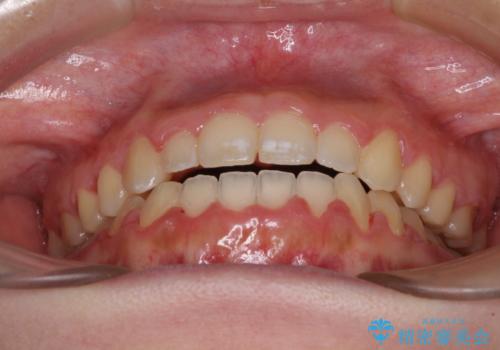

上顎骨を拡大したことで、下顎の歯列を上顎が受け入れられるようになりましたが、インビザラインでは咬み合わせを改善させることができなかったため、ワイヤー矯正にて仕上げることとしました。

ワイヤーを使用したものの、上下前歯のオープンバイトがなかなか改善されませんでしたが、患者希望により治療終了となりました。